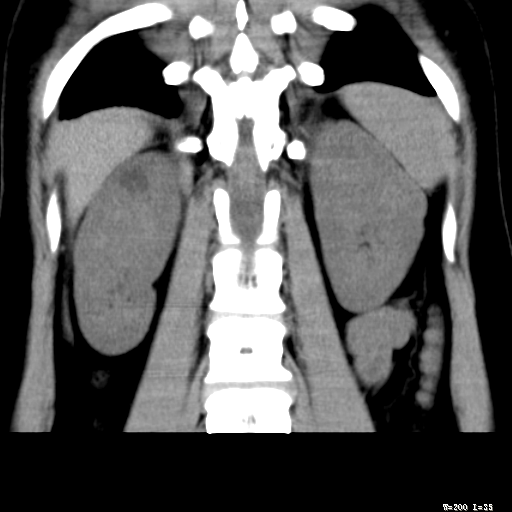

标题: CT25345:右肾占位。 [打印本页]

标题: CT25345:右肾占位。

女,30岁,右腰部胀痛3个月。

增强无明显强化,先考虑血管平滑肌脂肪瘤,建议作薄层扫描右mri检查,

感觉像囊肿.

囊肿!

考虑右肾近上极囊肿;建议必时行mri检查。